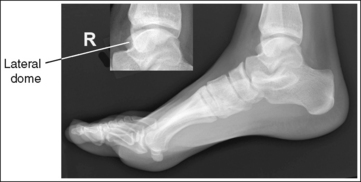

The calcaneus and distal tibia and fibula are in a lateral projection. The domes of the talus are superimposed, the tibiotalar joint space is open, and the distal fibula is superimposed by the posterior half of the distal tibia.

• Talar domes: The domes of the talus are formed by the most medial and lateral aspects of the talar's trochlear surface. They are visible on a lateral calcaneal projection as domed structures that articulate with the tibia. When a lateral calcaneus projection has been obtained, the talar domes should be superimposed and appear as one, and the tibiotalar joint should be open. If the lateral calcaneus is mispositioned, the domes are individually demonstrated and obscure the tibiotalar joint. Misalignment of the domes will result from poor knee and foot positioning.

• Effect of lower leg positioning on talar dome superimposition. Often, if the knee is not fully extended (Figure 6-42) or if the distal tibia is not elevated to place the lower leg parallel with the IR (in a patient with a large upper thigh), the proximal tibia is positioned farther from the imaging table than the distal tibia. The resulting image demonstrates the lateral talar dome proximal to the medial talar dome, and the height of the longitudinal arch appears less than it actually is because the cuboid shifts anteriorly and the navicular bone moves posteriorly in this position; the talocalcaneal joint will be narrowed (see Image 27). If the distal tibia is positioned farther from the imaging table than the proximal tibia, the medial talar dome is demonstrated proximal to the lateral dome, and the height of the longitudinal arch appears higher than it actually is because the cuboid shifts posteriorly, the navicular bone moves anteriorly, and the talocalcaneal joint will be wider (see Image 28).

When viewing a lateral calcaneal projection that demonstrates one of the talar domes proximal to the other, evaluate the height of the longitudinal arch and the degree of narrowing or widening of the talocalcaneal joint to determine which dome is the proximal dome. If the navicular bone is superimposed over more of the cuboid than expected and the talocalcaneal joint is narrowed, the lateral dome is the proximal dome; if the navicular bone is superimposed over less of the cuboid than expected and the talocalcaneal joint is wider, the medial dome is the proximal dome.

• Effect of foot positioning on talar dome superimposition. To demonstrate accurate AP alignment of the talar domes, the lateral surface of the foot should be positioned parallel with the IR. If this surface is not parallel with the IR, the talar domes are demonstrated with one anterior to the other. When the leg is rotated more than needed to place the lateral foot surface parallel with the IR, as shown in Figure 6-43, the medial talar dome is demonstrated anterior to the lateral talar dome (see Image 29). If the leg is not rotated enough to place the lateral foot surface parallel with the IR, as shown in Figure 6-44, the medial talar dome is demonstrated posterior to the lateral talar dome (see Image 30). When imaging a lateral calcaneus projection that demonstrates one of the talar domes anterior to the other, image the position of the fibula in relation to the tibia to determine how the patient should be repositioned. On most lateral calcaneus projections with accurate positioning, the fibula is positioned in the posterior half of the tibia. On a lateral calcaneus projection with poor positioning, if the fibula is demonstrated more posteriorly, the medial talar dome is anterior and the patient was positioned with the forefoot depressed and the heel elevated (leg externally rotated), as shown in Figure 6-43. If the fibula is demonstrated more anteriorly (leg internally rotated), the medial domes are posterior and the patient was positioned with the forefoot elevated and the heel depressed, as shown in Figure 6-44.